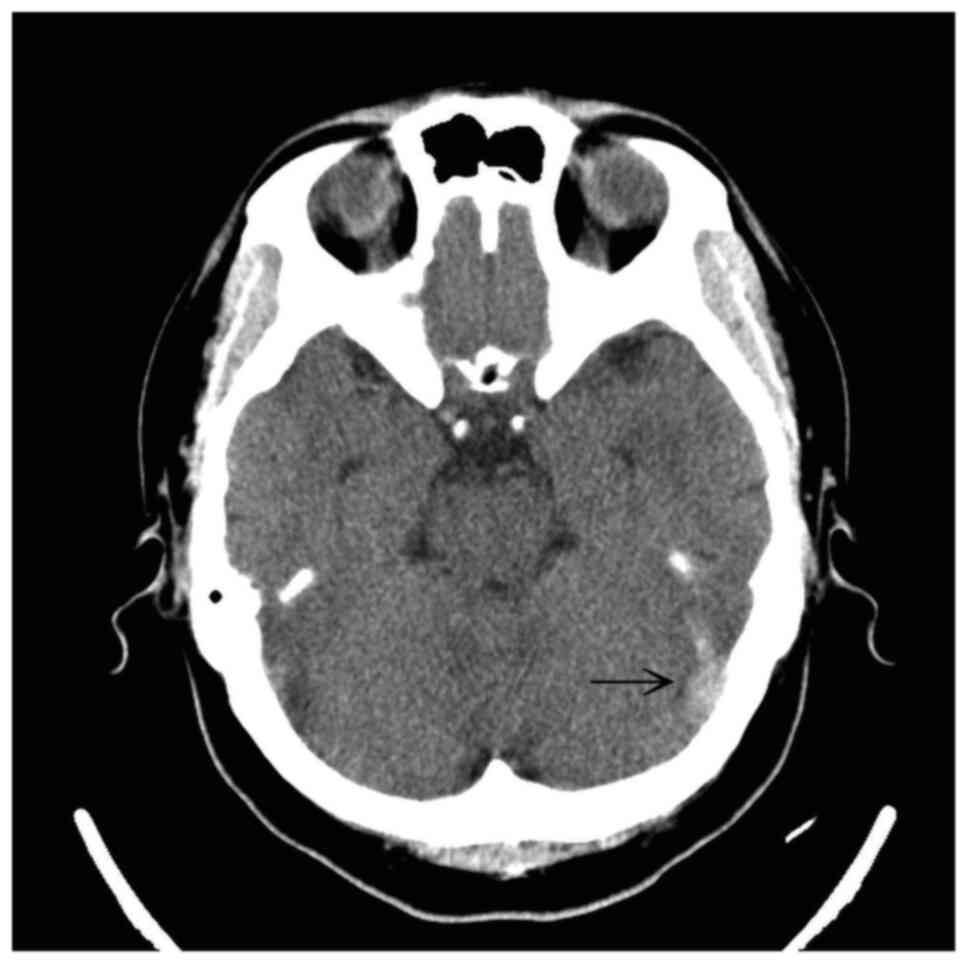

Figure 1

Computed tomography scan of the head illustrating an abnormal hyperattenuation (arrow) in the straight sinus and bilateral transverse sinuses.

A computed tomography (CT) scan of the head revealed an abnormal hyperattenuation in the straight sinus and bilateral transverse sinuses (Figs. 1 and 2). A diagnosis of CSVT was made following a consultation with a neurologist. The patient was treated with enoxaparin at 6,000 IU, levetiracetam at 1,000 mg and mannitol at 100 ml via an intravenous drip. Following admission, a magnetic resonance venography revealed the absence of flow in the straight sinus and bilateral transverse sinuses (Fig. 3). A thrombophilic investigation revealed a plasma homocysteine level of 59.03 µmol/l (upper normal limit, 15.39 µmol/l) and a vitamin B12 level of <148 (lower normal limit, 187 pg/ml). The levels of protein C (70-140%), protein S (60-130%) and antithrombin III (75-125%) were within the normal range. CSVT secondary to homocystinemia was diagnosed, which is an unusual, yet treatable condition.